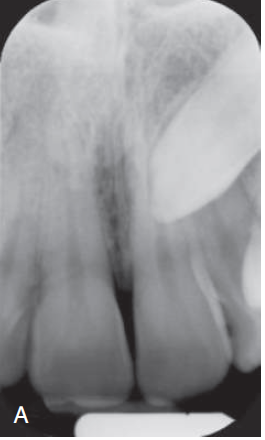

1. (Select ONE OR MORE correct answers)

The radiograph shows evidence of